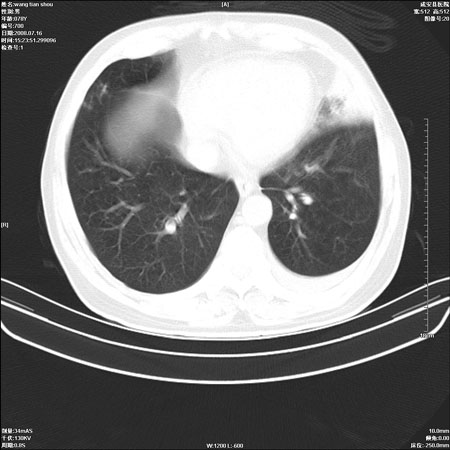

以下是引用qingjing在2008-7-16 19:55:00的发言:[br]1、左上肺不张并堵塞性炎症,建议支气管镜详查;[br]2、左侧胸腔少量积液。

以下是引用wzr在2008-7-16 20:26:00的发言:[br]左肺肺不张伴阻塞性肺炎!另:左侧胸腔少量积液。建议纤支镜检查!